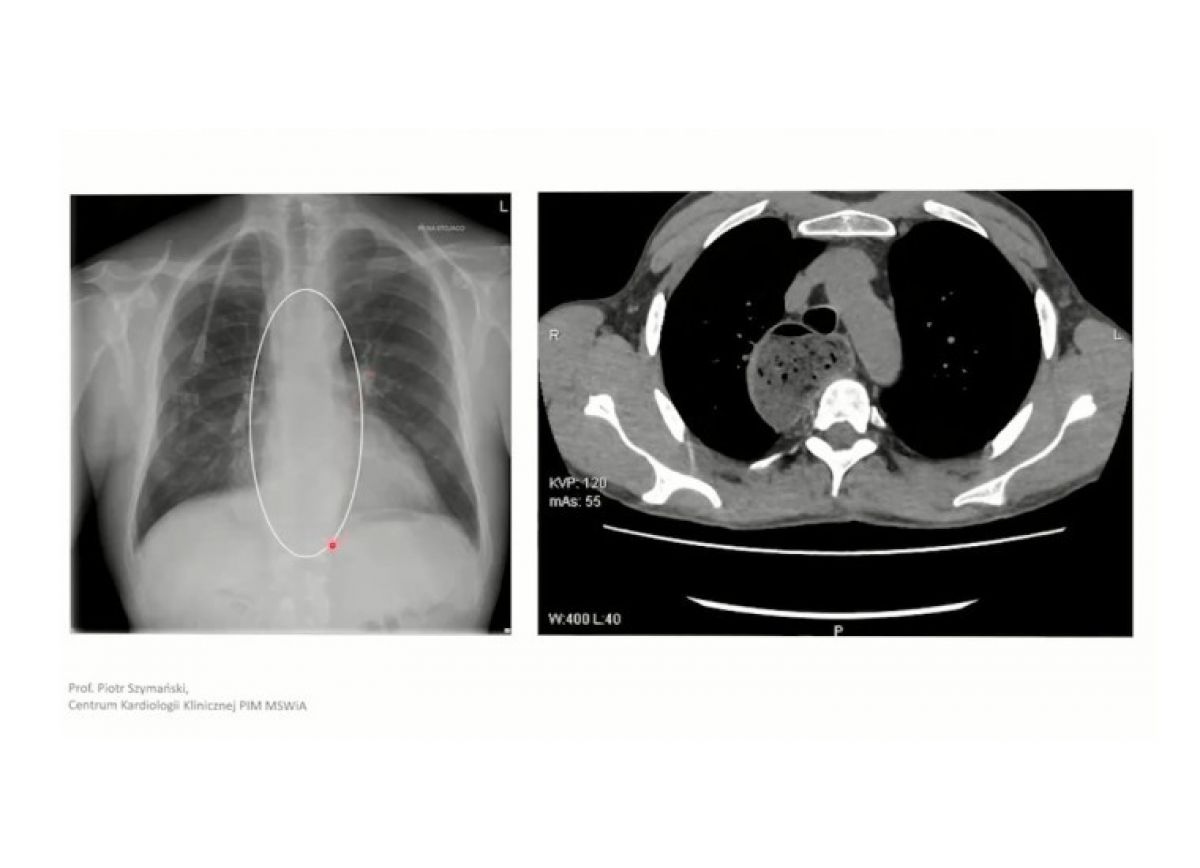

Pacjentka z niewydolnością nerek

Łagodne zwężenie zastawki aortalnej

Przerost mięśnia lewej komory z dysfunkcją rozkurczową

Achalazja przełyku